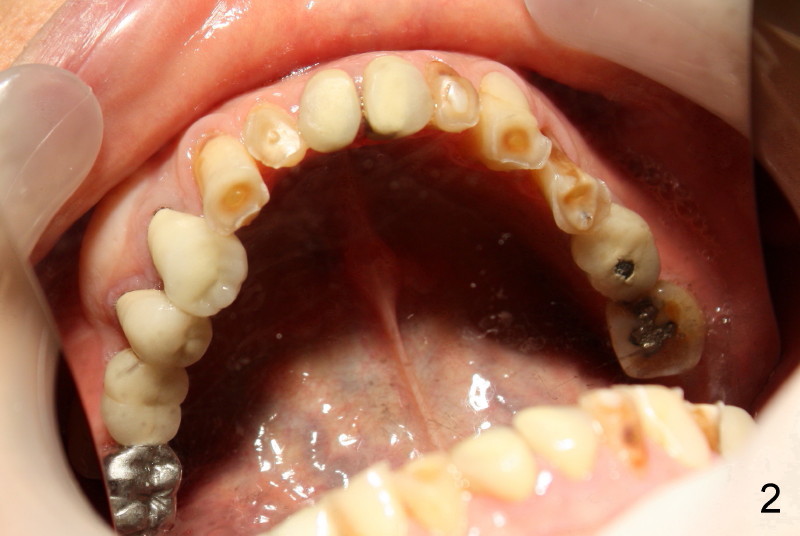

Sixty-five year old man is a bruxer, as shown in Fig.1, 2 (upper. lower arch, respectively, mirror view).  He has a night guard.  Fig.1-3 and Fig.4,5 are taken before and after crown fracture of the tooth #9, respectively.  It appears that the tooth is nonsalvageable.